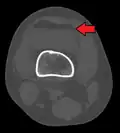

Diagnosis

In all injuries to the tibial plateau radiographs (commonly called x-rays) are imperative. Computed tomography scans are not always necessary but are sometimes critical for evaluating degree of fracture and determining a treatment plan that would not be possible with plain radiographs.[10] Magnetic Resonance images are the diagnostic modality of choice when meniscal, ligamentous and soft tissue injuries are suspected.[11][12] CT angiography should be considered if there is alteration of the distal pulses or concern about arterial injury.

3D reconstruction of a CT image of a tibial plateau fracture -